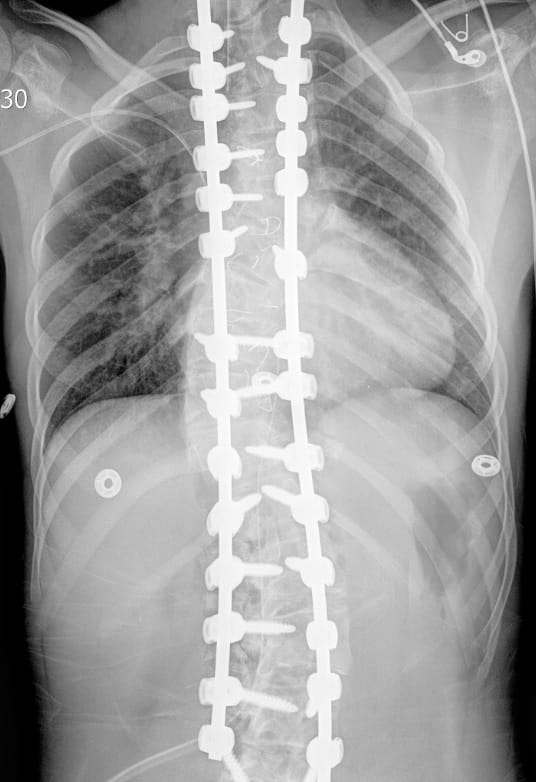

X-ray of spine after procedureAfter instrumentation and fusion, her curves measure less than 20 degrees with excellent correction in coronal and axial planes.